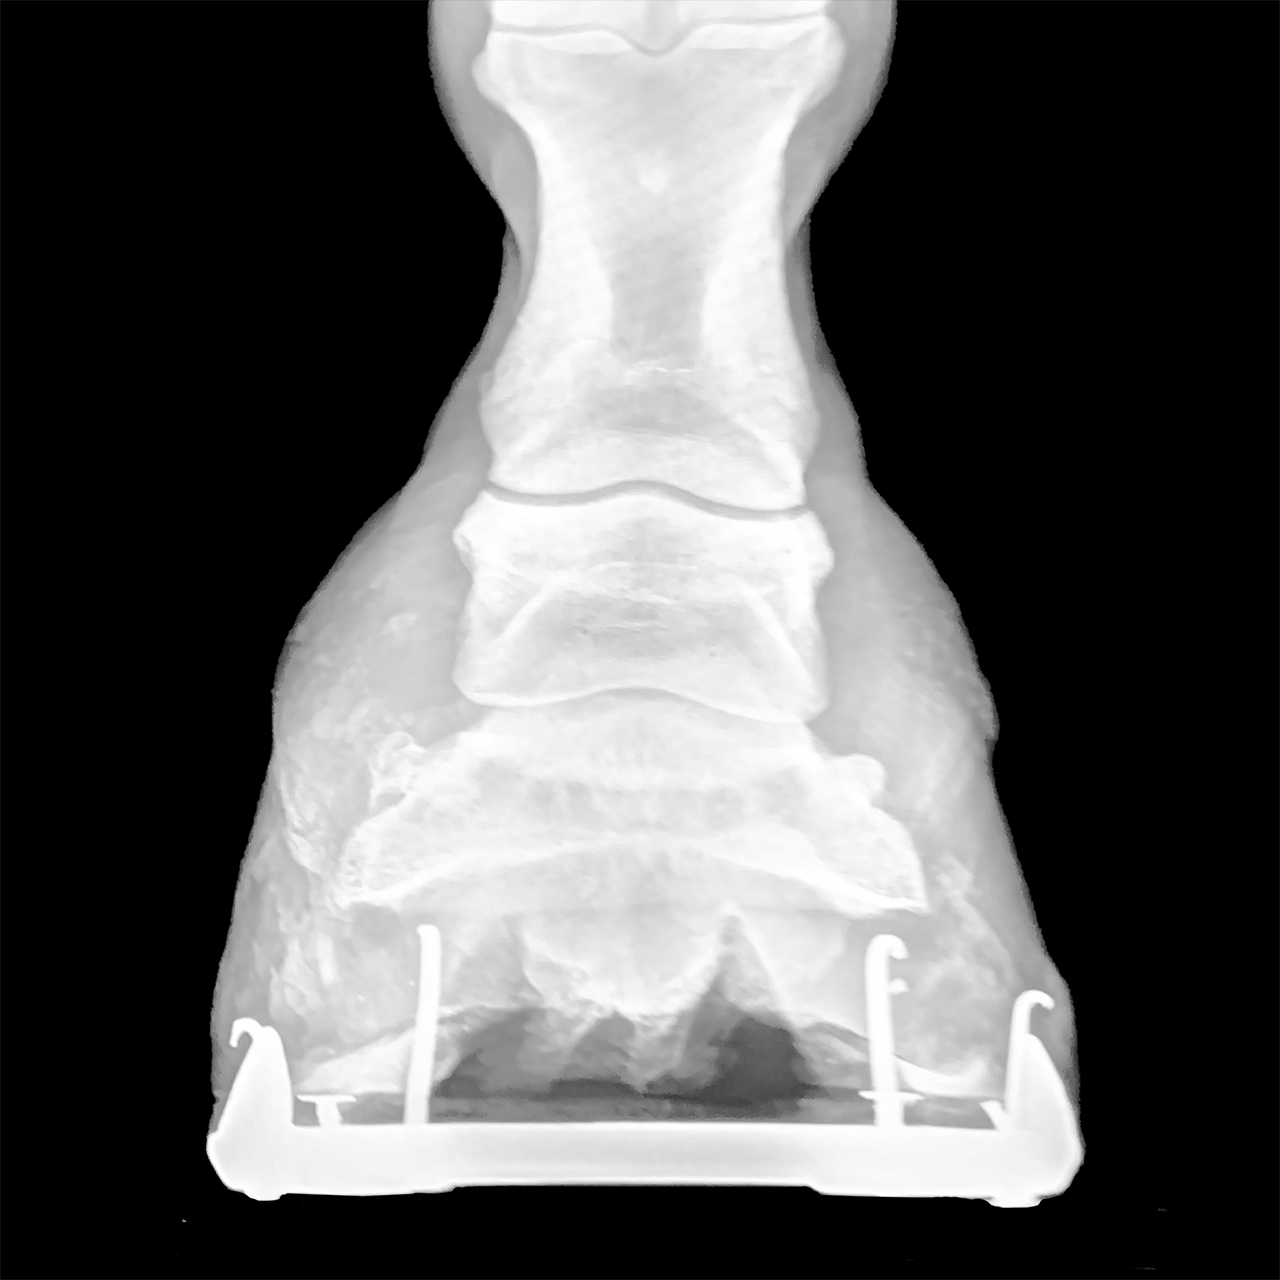

Excessive Distance Between the Coffin Bone and Ground Surface

CALCULATE PAD THICKNESS TO CORRECT HOOF ANGLE

RECOGNIZE THE NEED FOR SUPPORT

DETERMINE THE PROBLEM AND PLAN